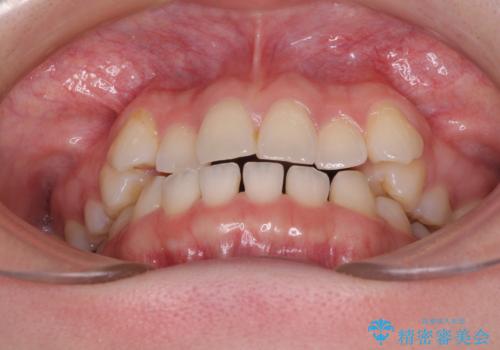

- 八重歯を気にして来院された患者様です。

口腔内の状況を確認したところ、左右ともに下顎第二大臼歯が欠損しており、咬み合うべき上顎の第二大臼歯が著しく挺出していました。

挺出した大臼歯を元の位置に戻すことは現実的に難しいため抜歯することとし、補助装置とワイヤー装置により上顎歯列全体を後方に移動することとしました。